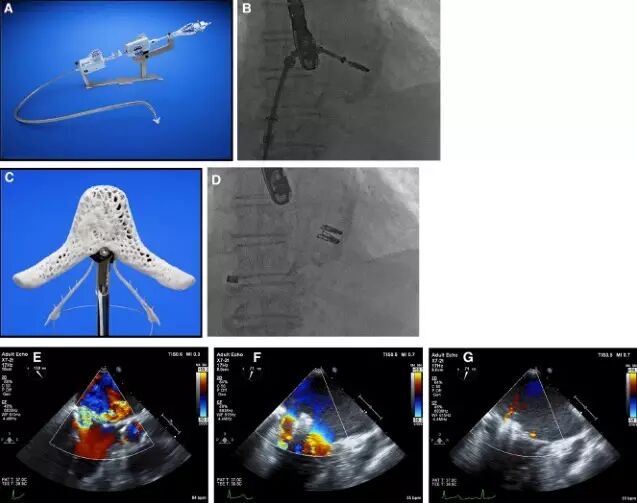

尚有治疗MR的处于临床I期的其他方法,比如 NeoChord, Mitra-Spacer, MitraSpan, MitraFlex, and V-Chordal,如图3所示

图3 Carillon间接成形术(A), Mitralign 直接成形术(B), enCor 二尖瓣环环缩术(C)NeoChord人造腱索及其配套传送装置(D)。

图5 CardiaQ (A),Tiara (B),Fortis (C),Lutter/Tendyne (D)